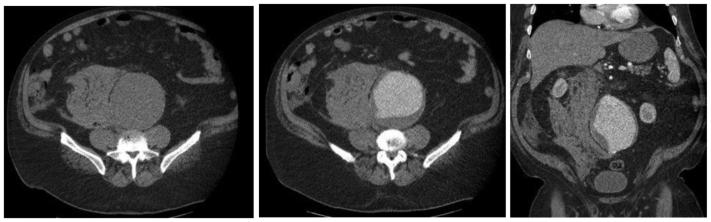

A primary aortocaval fistula (ACF) is a rare complication of abdominal aortic aneurysms caused by erosion of the aortic wall into the vena cava. It is more frequently observed in the setting of ruptured abdominal aortic aneurysms and presents a unique challenge for vascular surgeons. Both open and endovascular techniques exist, with the main differences being perioperative mortality and recurrence rates. We present a case of an ACF diagnosed intraoperatively, which persisted after endovascular aneurysm repair in conjunction with a type II endoleak. We applied a unique staged, triple endovascular approach to close the ACF via caval and aortic exclusion of inflow and outflow vessels.

原发性主动脉腔静脉瘘(ACF)是腹主动脉瘤的一种罕见并发症,由主动脉壁侵蚀进入腔静脉所致。在破裂性腹主动脉瘤中更常观察到,对血管外科医生构成独特挑战。开放手术和血管内技术都存在,主要区别在于围手术期死亡率和复发率。我们报告一例术中诊断为ACF的病例,该病例在血管内动脉瘤修复术后伴有II型内漏持续存在。我们采用了一种独特的分期、三重血管内方法,通过腔静脉和主动脉对流入和流出血管的封堵来闭合ACF。